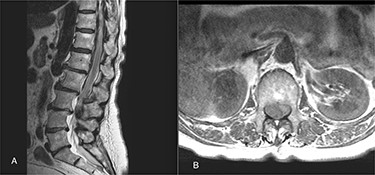

On 17 February 2020, she underwent TKA (Fig. 1). Spinal anesthesia was performed, with the patient in sitting position with one laborious puncture, as referred by the anesthesiologist. The patient received low molecular weight heparin (4000 UI enoxaparin sodium) subcutaneously 12 h after the surgery and a second shot dose 24 h later. On the second post-operative day (19 February 2020), early in the morning, the patient complained of numbness in her lower extremities and low back pain, partially relieved with analgesics. Four hours later, she was complaining for severe difficulty in moving her legs with increased low back pain. The physical examination showed flaccidly paralyzed left lower leg (0/5 left quadriceps, 0/5 left extensor digitorum longus, 0/5 left tibialis anterior and 0/5 left extensor hallucis longus), marked motor function reduction of the right lower leg (1/5 right quadriceps, 2/5 right extensor digitorum longus, 2/5 right tibialis anterior and 2/5 right extensor hallucis longus), sensory loss in both lower limbs, Babinski sign negative bilaterally and preserved sphincter functions. Magnetic resonance imaging (MRI) was required to rule out an acute spinal compression. The images showed a spindle-like mass, mostly intradural, from T11 to L3, hypointense in T2 and heterogeneous in T1 images compressing the dural sac (Fig. 2). Therefore, a diagnosis of acute spinal hematoma was made, and the patient was transferred to the Neurosurgery Department, and surgical decompression was scheduled. A bulky blood clot was removed through a spino-hemilaminectomy of T11 and T12 followed by a posterior dural incision. The source of bleeding was identified in a perimedullary vein on the dorsal surface of the spinal cord that was coagulated. Surgery was performed 3 h after diagnosis, and few hours later, the patient was able to perform a flexion-extension of both lower limbs. She was able to start walking with a walker 24 h later. A low molecular weight heparin (2000 UI Enoxaparin sodium) subcutaneously was started 1 week after surgical decompression. This dosage was increased to 4000 UI 2 days later. On 24 February 2020, a follow-up MRI was performed, and it showed a partial resolution of the hematoma with a confined area of myelopathy at the T12 level (Fig. 3). On the 26 February 2020, the patient started the rehabilitation protocol with the gradual improvement of the neurological status.

(A) The sagittal T2 FSE MRI show hypointense spindle-like mass from T10 to L3; (B) axial T1w FSE MRI showed iso-hyperintense hematoma compressing the dural sac (L1 level).